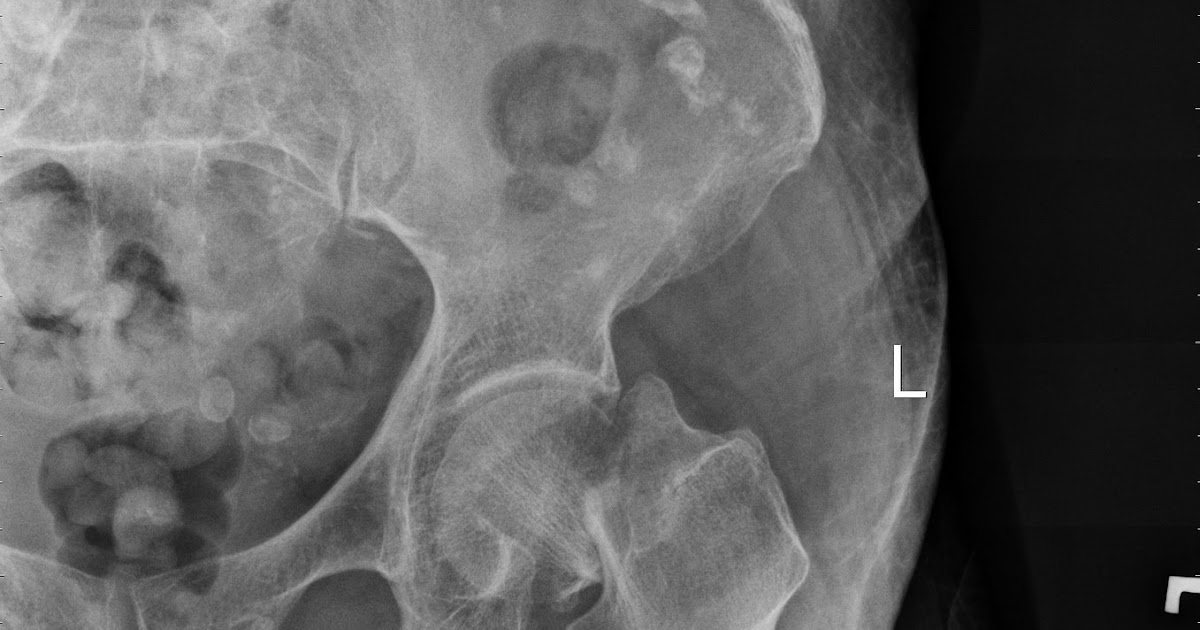

Most hip fractures can be diagnosed with a xray. Related online courses on physioplus.

Osteoporotic hip fractures in 4344 patients were more common during winter. Some non displaced fractures require a ct scan or single shot mri. Related online courses on physioplus. Hip fractures either involve bone enveloped by the ligamentous hip joint capsule (intracapsular) or the bone below the capsule (extracapsular). It covers icd codes 800 to 999. In the vast majority of cases, a hip fracture is a fragility. International classification of disease, ninth revision, clinical modification. This website summarizes the care pathway for all hip fracture patients admitted to ucsf. These patients will be followed by. Knee assessment and hip mechanics online course: Revise new code new code new code new code. Osteoporotic hip fracture is a major complication of systemic inflammation. Ebraheim's educational animated video describes fractures of the hip, types, signs and symptoms, etiology and specific fixation methods.this is a quick. All formats available for pc, mac, ebook readers and other mobile devices. You can get the best discount of up to 50% off. Other osteoporosis without current pathological fracture: You can always come back for icd code for hip fracture because we update all the latest coupons and special deals weekly.